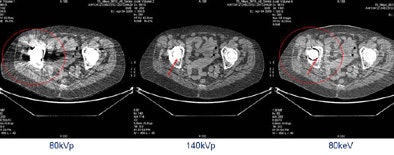

Superior optical properties are what enable CT750 HD's high-definition generator to acquire approximately 2,250 images per second, electronically switching tube energies from 40 kVp to 120 kVp to acquire dual-energy images with a single x-ray tube during operation, Stahre explained. Dual-energy imaging using a single x-ray source is the system's other key capability.

Pulsing rapidly from low (40 kVp) to high (120 kVp) and back again, each exposure takes about 0.5 msec -- about a quarter of the time it takes to blink an eye. The switching is electronically controlled, and because each energy burst is so short, image quality is improved while dose is reduced, Smith said.

The dual-energy-signal views enable the user to dial into an interpolation of the precise energy that shows the pathology best, or, for example, eliminates calcium and its blooming artifacts, which can improve visualization of noncalcified regions.

In orthopedic applications, modification of tube energies can eliminate beam-hardening artifacts, though research in dual-energy CT imaging is sparse. Smith said he sees great potential in many other areas.